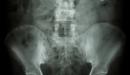

يحتوي الجهاز العظمي للإنسان على عدد كبير من العظام يقدر عددها بـ206 عظمة، ويؤدي هذا الجهاز عدداً من الوظائف الحيوية والمهمة تتمثل في الدعامة وإعطاء شكل الجسم، وحماية الأعضاء الداخلية وتقليل خطر الإصابة، وإنتاج خلايا الدم في نخاع العظم، بالإضافة إلى أنّ العظام تشكل مخزناً للدهون والأملاح مثل الكالسيوم والفسفور وغيرها.

يشكل ضعف العظام أو ما يُعرف بمرض هشاشة العظام أحد الأمراض الأكثر انتشاراً والذي يتمثل في ضعف وترقق العظام نتيجة لانخفاض مستويات الكالسيوم في الجسم، مما يسبب ألماً شديداً في العظام ويجعلها أكثر عرضة للكسور، بالإضافة إلى تغيير بنية العظام الطبيعية، وبالرغم من الاعتقاد السائد بأنّ هذا المرض يصيب في الغالب الإناث، إلا أنّ هشاشة العظام تصيب الذكور أيضاً.